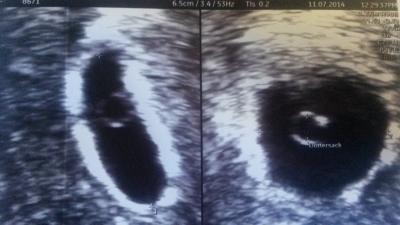

Guten morgen Gestern hatte ich meinen ersten Termin beim FA.. auf dem US war ein "wunderschöner" Dottersack zu sehen.. mein Arzt war voll aus dem Häusschen Sieht alles sehr gut aus, sitzt alles dort wo es hin gehört,.. Er schätzt mich in Wo 5... In 14 Tagen muss ich wieder hin, dann bekomme ich auch den Mutterpass! Juchuh!

Bild zu kleine Erleichterung - Forum für März - Mamis